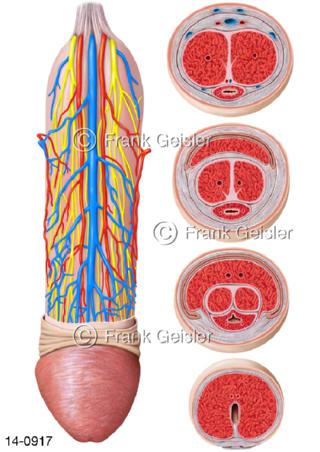

Bildergalerie Urogenitalsystem

Bilder zum Urogenitalsystem mit Urogenitalorgane, Urogenitaltrakt, zum Harn- und Geschlechtsapparat, Harnorgane und Geschlechtsorgane, Organe der Harnwege und der Fortpflanzung, Harnorgane und Geschlechtsorgane im männlichen und weiblichen Urogenitalsystem